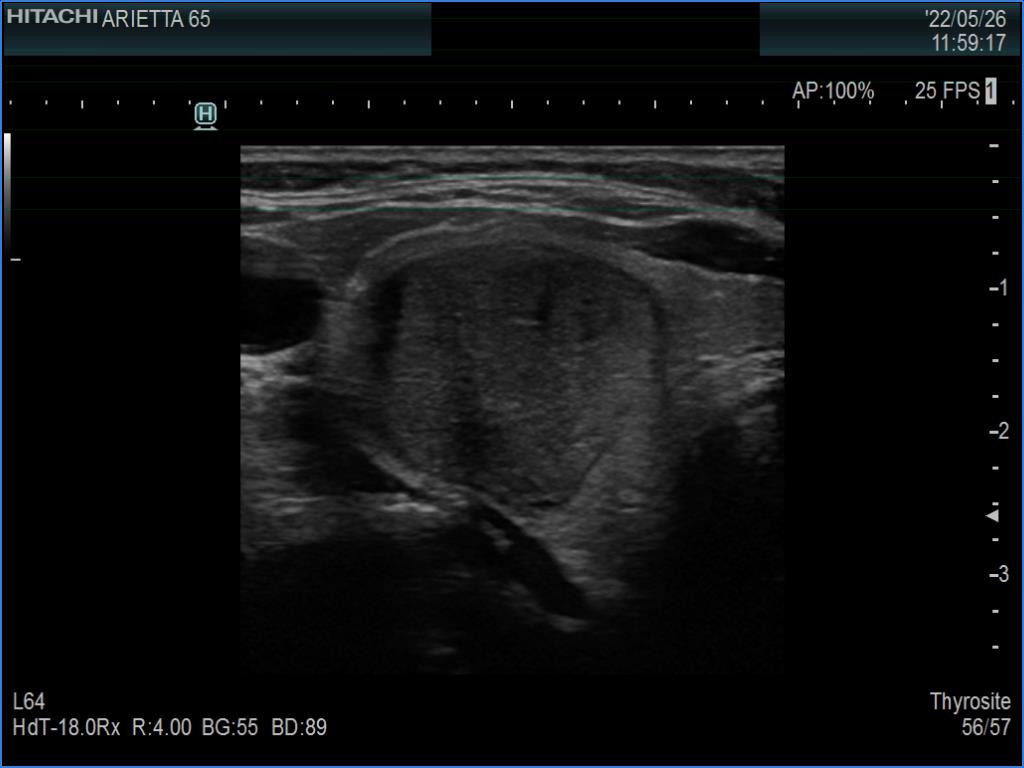

Ultrasonography. The thyroid was echonormal. There was a moderately hypoechoic nodule in the right lobe. The nodule has halo and presents with a combined perinodular and intranodular blood flow. The latter was irregularly increased.

The presentation of the nodule is not very suspicious. Halo sign is a rare finding in medullary cancers.

The classification of the nodule depends on the judgement of nodule borders. If it is regarded as irregular, then the lesion is an EU-TIRADS 5 one. However, if we judge the borders as non-lobulated, then the lesion is an EU-TIRADS 4 nodule. According to the EU-TIRADS, FNA is indicated in both cases because the largest diameter of the nodule exceeds 15 mm.